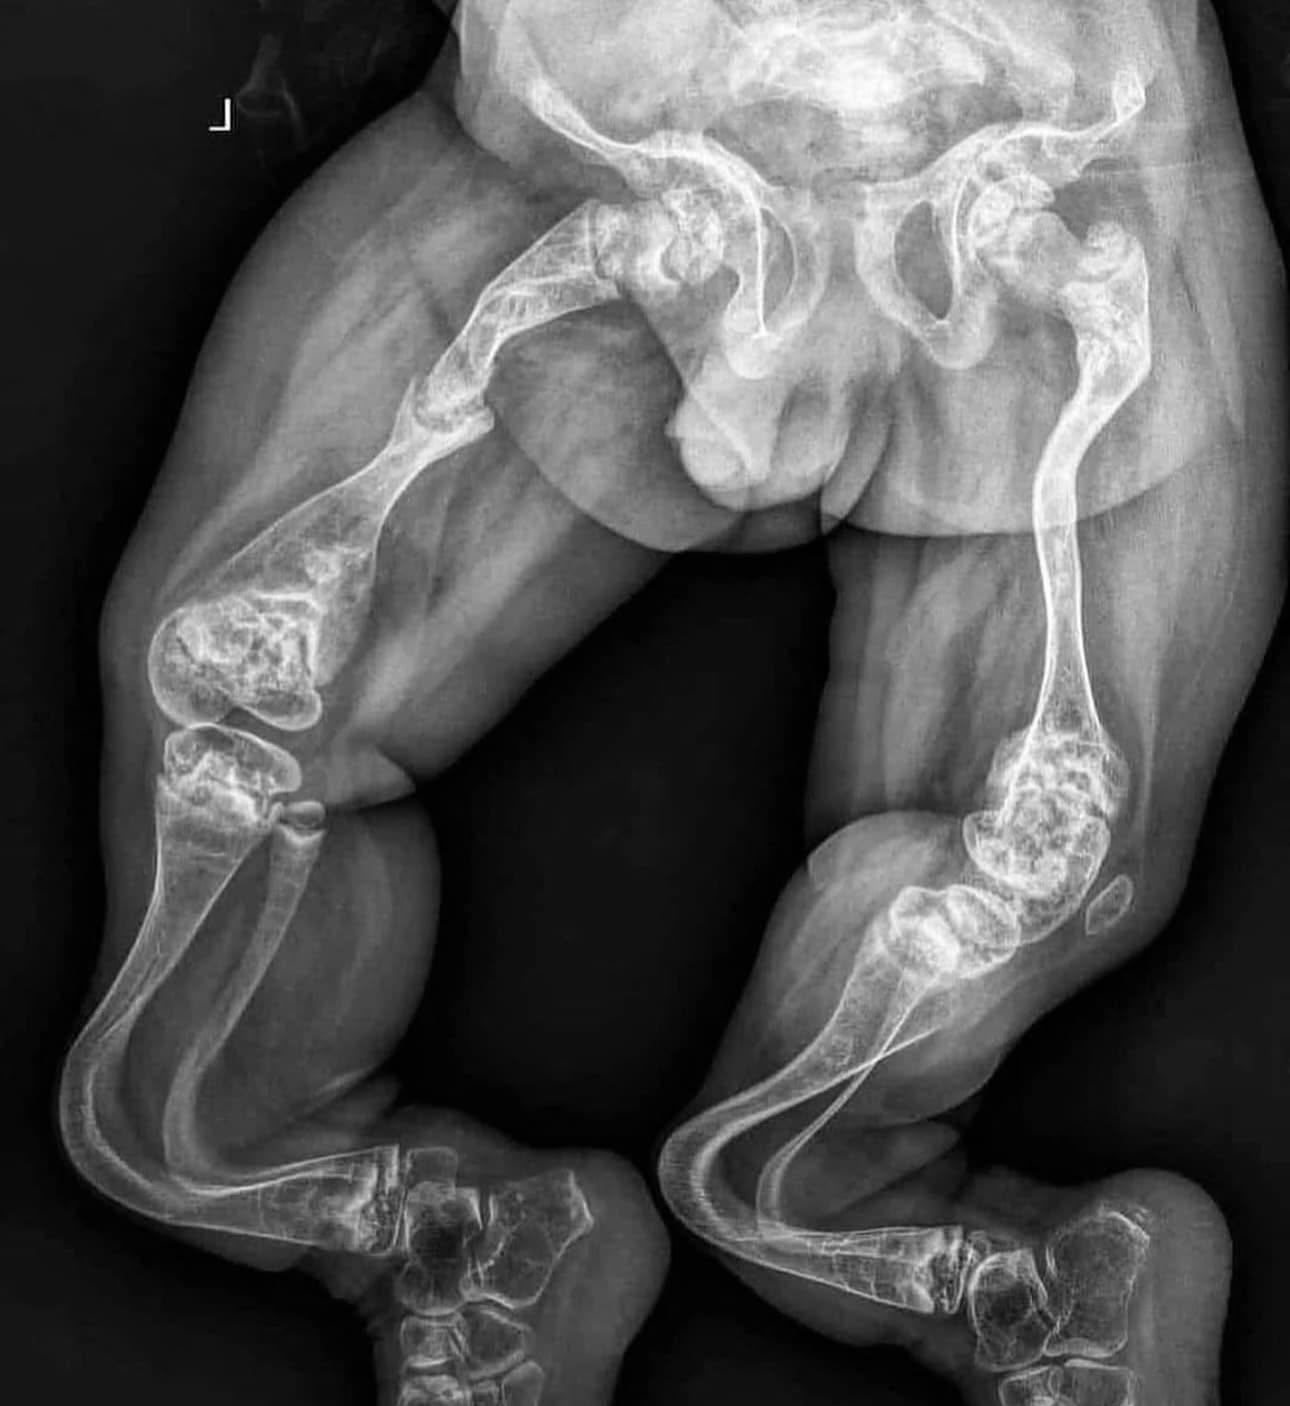

Батьки привезли дитину з такою рентгенологічною картиною. Подумайте який діагноз ви можете запідозрити і дайте відповідь нижче.